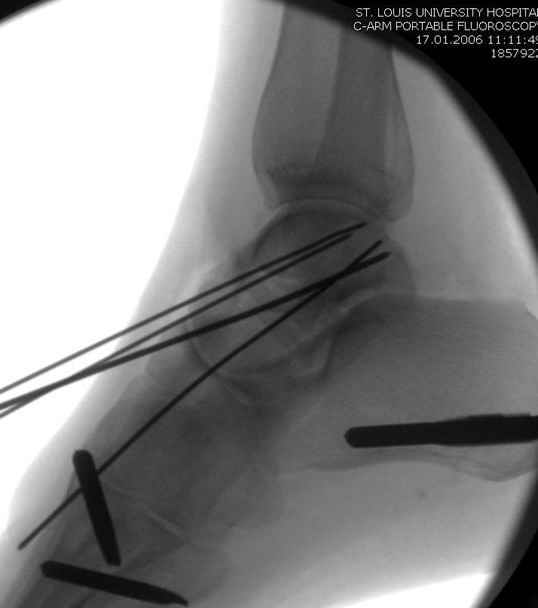

Вдогонку по поводу перелома таранной кости, больная 81, не страдает диабетом, перелом закрытый, в первый же день поступления ограничились временным наружным фиксатором (как на снимке).

Планировалась открытая фиксация после спадения отека, но больная пожелала лечиться по месту жительству в другом штате..

Из-за отека на стопе тактика лечения у всех была

одинаковая: временная наружная фиксация до спадения отека, при изолированных переломах они выписывались домой и через дней 7 госпитализировались на оперативное лечение.

Примеры на снимке...